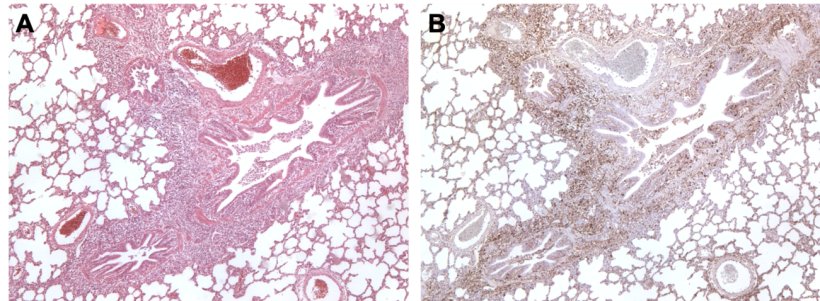

Hình 3. Phổi heo bị nhiễm đồng thời bởi M. hyopneumoniae and PCV2. A: Khu vực tăng sinh lympho quanh tiểu phế quản do M. hyopneumoniae gây ra. B: Lượng lớn kháng nguyên PCV2 trong cùng khu vực tăng sinh lympho này.